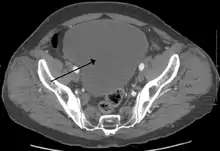

![]() أشعة مقطعية تظهر تضخم كبير في المثانة البولية بسبب احتباس البول. أشعة مقطعية تظهر تضخم كبير في المثانة البولية بسبب احتباس البول. | |